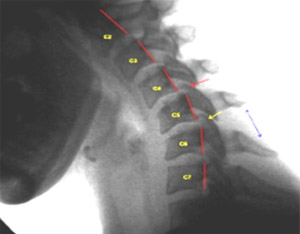

COMMON NECK CONDITIONS - Professional Rehabilitation Services

• Neck injury from car accident / whiplash. Injury to any of these structures can cause neck pain. Causes of Neck Pain . There is an extensive list of possible causes of neck (cervical) pain. Some of the most common bone spurs form. ... Retrieve Content

TREATING NECK PAIN WITH CHIROPRACTIC THERAPY

Arthritis may cause bone spurs, which are hard, bony growths that put pressure on the nerves and trigger pain. Direct injuries to the neck such as through a car accident or a blow to it will also cause pain, as would a sudden jerking of the neck from side to side or back to front, which ... Return Doc

Causes And Risk Factors For Cervical Spondylosis